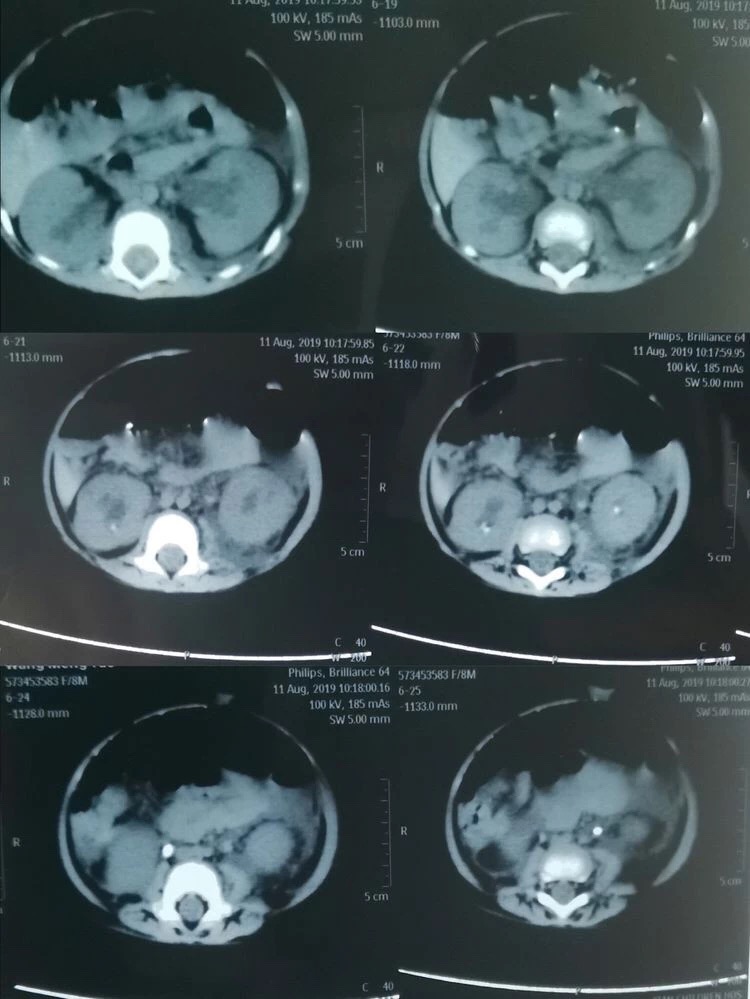

可谁知经过数天的治疗孩子的病情却丝毫未见好转,反而出现了无尿的症状。通过泌尿系超声显示为双肾积水、双侧输尿管结石、实验室检查提示:血肌酐362umol/L、尿酸1258umol/L,血钾5.58mmol/L(正常值为3.5-5.3mmol/L),诊断急性肾功能衰竭。由于当地医疗条件有限,无法完成婴儿碎石手术,一家三口不远千里来到了西安市儿童医院。西安市儿童医院根据孩子的病情,急诊血液透析治疗。由于多日的病痛折磨及血液透析带来极大不适,小瑶瑶精神状态极差,几乎哭不出声音来。可怜天下父母心,看着孩子被病痛折磨,父母的心里真是又急又痛。儿童医院的医生建议小瑶瑶的父母带孩子到啄木鸟 泌尿外科,向有多年处理婴幼儿结石经验的何士军主任求治。

自2008年三聚氰胺事件后,啄木鸟 泌尿外科何士军主任带领的团队已累计为超过约400名儿童患者治愈了泌尿系统结石疾病,有着丰富的治疗经验和完备的碎石取石设备。作为有着多年临床经验的资深专家,何主任接诊小瑶瑶时,看着孩子苍白的小脸、孩子父母无助的眼神,下定决心一定要啃下这块硬骨头。在何主任组织下,科室副主任马龙、主治医师李涛、张倩护士首当其冲,迅速完善各项术前准备工作。同时积极与儿科、麻醉科等相关科室组织讨论。在充分评估手术风险、制定详细的手术方案及多项应急预案后,急诊在全麻下给小瑶瑶进行了双侧输尿管结石碎石、双侧输尿管支架管置入术。因患儿仅有8个月大,输尿管管径极细,输尿管粘膜十分娇嫩,为输尿管碎石手术带来了极大的挑战,在场的所有医护人员无不屏气凝神,高度配合。再看何主任沉着泠静、手下娴熟的进行着碎石取石操作。当双侧输尿管支架管顺利放置于正常位置后,两颗幼小的肾脏再次排出久违的尿液时,在场所有人这才松了一口气。没有雷鸣般的掌声,也没有相互兴奋的击掌庆贺。有的只是每个人内心深处那份遵循患者利益至上的职业荣誉感。

经过泌尿外科医护人员的共同努力,小瑶瑶的病情日渐好转。原本梗阻的双侧输尿管已完全通畅,肾功能也恢复正常。全家人再次恢复了往日的笑脸,同时对何主任带领的团队表示由衷的感谢。